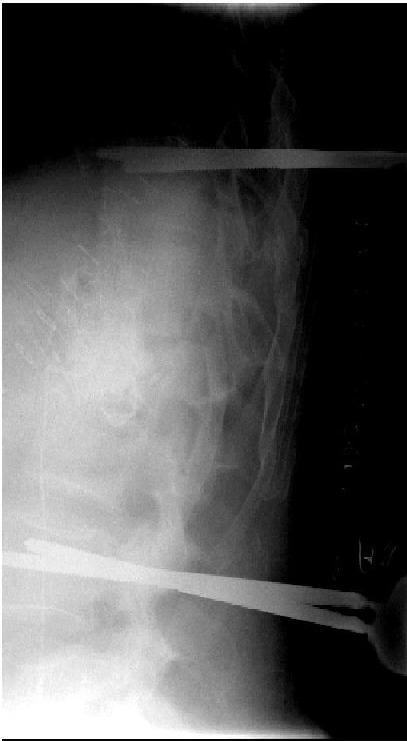

Specific and non-specific infections of the spine are rare. Due to their potential for severe instabilities, deformities and the impairment of neurological structures, the treatment is often prolonged and needs an interdisciplinary management. The clinical presentation is uncharacteristic, therefore diagnosis is often delayed. There are no prospective randomized studies for therapy recommendation. The surgical concept includes eradication of the infection and the reliable stabilization of involved segments. This concept is successful in most cases of endogenous vertebral osteomyelitis. The therapy of the exogenous spine infections after macro and micro surgery is more difficult, due to the critical wound situation and the involvement of the posterior parts of the spine. In these cases, infection-associated instability of the anterior part is complicated by critical posterior wound conditions. We present three cases of severe exogenous vertebral infections, where temporary external transpedicular spine fixation was used for salvage procedure, till soft tissue conditions have permitted a definitive internal stabilization.

脊柱的特异性和非特异性感染较为罕见。由于它们可能导致严重的不稳定、畸形以及神经结构受损,治疗往往较为漫长,且需要多学科管理。临床表现不典型,因此诊断常常延迟。目前尚无用于推荐治疗方法的前瞻性随机研究。手术理念包括根除感染以及对受累节段进行可靠的稳定固定。这一理念在大多数内源性椎体骨髓炎病例中取得了成功。由于伤口情况危急以及脊柱后部受累,宏观和微观手术后外源性脊柱感染的治疗更为困难。在这些病例中,前部感染相关的不稳定因后部伤口情况危急而变得复杂。我们展示了三例严重的外源性椎体感染病例,其中采用了临时经椎弓根外固定脊柱进行挽救手术,直至软组织条件允许进行最终的内固定。